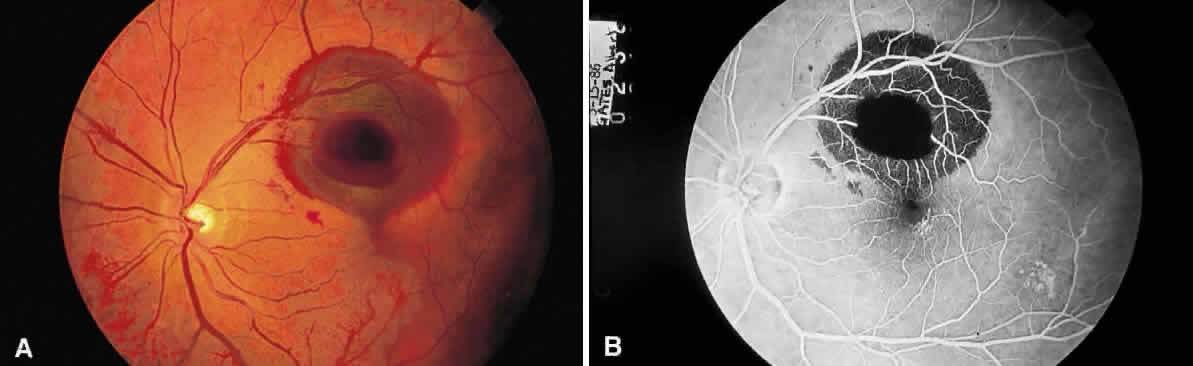

The pink color of the normal optic nerve head is reflective of the vascular supply to the surface of the disc. Loss of the vascularity or replacement of the neural tissue by opaque glial tissue alters the color of the disc (Fig. 7). Anatomical variations in the retina alter the appearance of lesions, in particular, the macula and the retinal periphery. The macular cytoarchitecture differs in that the ganglion cell layer and nerve fiber layers are displaced centrifugally from the fovea. Therefore, on ophthalmoscopic examination, conditions that affect these layers are not apparent in the fovea. Tay-Sachs disease involves the accumulation of storage material by ganglion cells. Since these cells are not present in the fovea and the presence of the storage material opacifies the normally transparent retinal tissue, the retina surrounding the fovea is opacified, but the fovea transmits the normal choroidal color (red), accounting for the presence of the “cherry-red spot” in this condition. Notice that the opacification (white appearance) of the perifoveal retina is not seen beyond the macula. The reduced concentration of ganglion cells in the extramacular retina explains the focal nature of this retinal opacification (Fig. 8). The oblique orientation of the outer plexiform layer (connection of rods and cones to the bipolar layer) in the macula explains the appearance of several lesions. Cyst-like spaces may occur at the level of the outer plexiform layer of the macula (Henle's layer) as the result of the accumulation of fluid or the hydropic swelling of Müller cells with subsequent disruption and the formation of the spaces.1,2 These cyst-like spaces (they are not lined by an epithelium and are therefore not designated as true cysts) are oriented along the plane of Henle's layer and appear to originate from a central zone (Fig. 9), like the petals of a flower. The fluorescein angiographic appearance of cystoid macular edema is frequently described as having a petaloid pattern3 (Fig. 10).

Fig. 9. Section through the fovea and macula demonstrating cystoid macular edema. Cyst-like spaces are present in the outer plexiform layer. (Courtesy of Ralph C. Eagle Jr, MD, Philadelphia, PA)

Fig. 10. Fluorescein angiographic appearance of cystoid macular edema described as having a “petaloid pattern.”